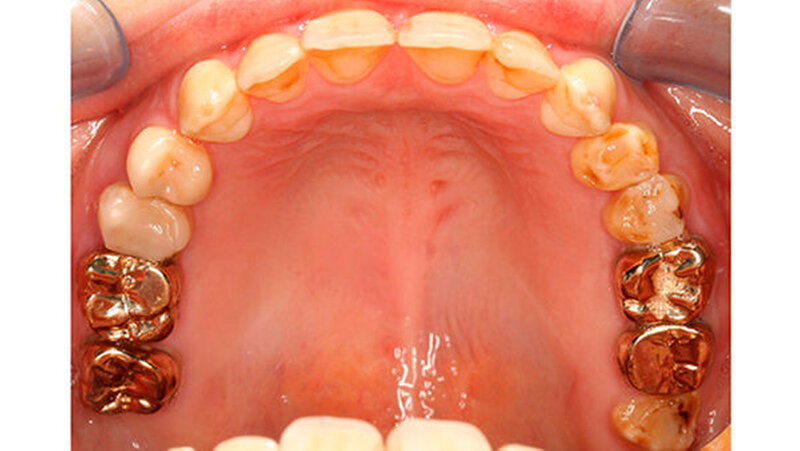

Mit dem Durchbruch der ersten bleibenden Molaren treten dann bisher unbekannte Beschwerden auf wie zum Beispiel eine übermäßig ausgeprägte Kälte-/Wärmeempfindlichkeit. Für manche Kinder wird dadurch nicht nur die Mundhygiene sondern auch die Nahrungsaufnahme erschwert. Zusätzlich bricht oft schon in der Durchbruchs-Phase der Schmelz ein (Abbildung 1), was die Überempfindlichkeit in teils akute Zahnschmerzen übergehen lässt.

Das klinische Bild der MIH reicht von einem bis zu vier betroffenen Molaren, nur selten sind alle Zähne in ähnlicher Ausprägung geschädigt [Weerheijm et al., 2001]. Die bleibenden Frontzähne können ebenfalls betroffen sein, diese weisen allerdings in der Regel keinen Schmelzeinbruch auf und sind selten bis gar nicht überempfindlich [Weerheijm et al., 2001] (Abbildung 2).